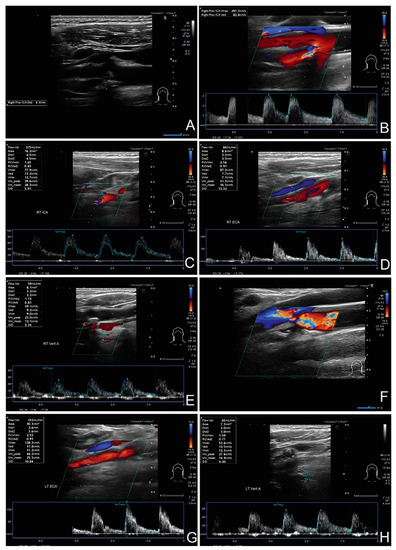

2. Materials and Methods

3.3. The Pathways of Volumetric Flow Compensation in the Extracranial Arteries

- 23 contralateral ICA

- 16 contralateral ECA

- 17 contralateral VA

- 23 ipsilateral ECA

- 22 ipsilateral VA.